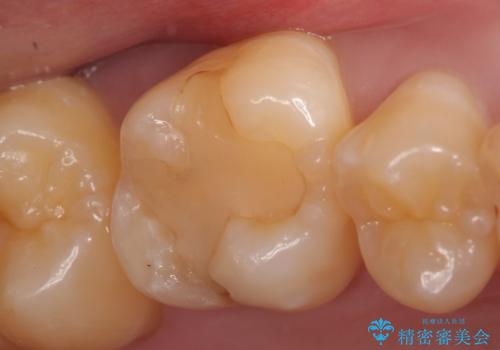

- 右上6番目の歯がしみるので診て欲しいといらっしゃった方の症例です。

古い樹脂が欠けており、そこから虫歯になっていたため、PGA(ゴールド)インレーによる修復を行いました。